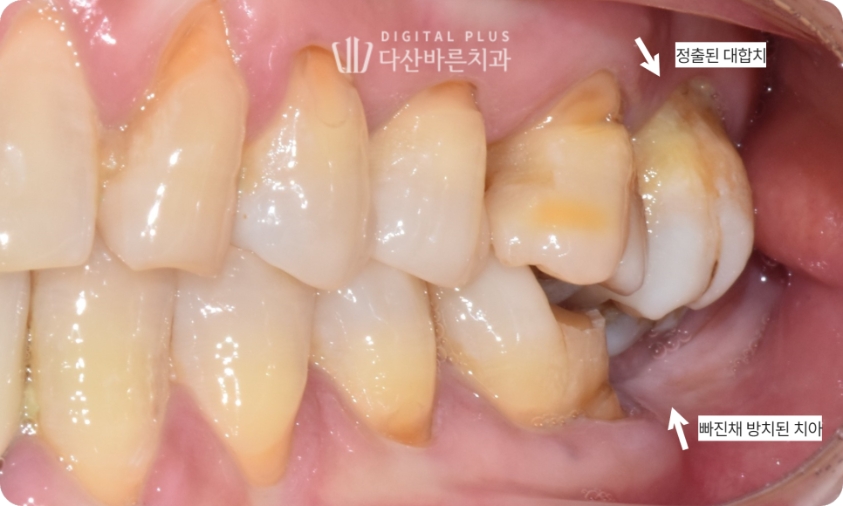

▲ 초진 시 구강 사진. 왼쪽 아래 어금니를 빠진 채 방치하여 위 대합치가 정출된 상태.

▲ 치료 완료 후 구강 사진(좌측).

충치가 있었던 인접치들까지 깔끔하기 치료한 뒤 최종적으로 치료가 마무리됐는데요.

정출된 치아로 무너진 교합과 치아 배열까지 깔끔하게 정리된 모습입니다.